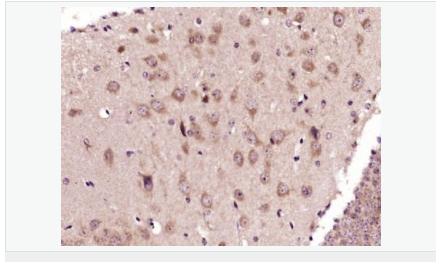

| 產(chǎn)品應(yīng)用 | WB=1:500-2000 IHC-P=1:100-500 IHC-F=1:100-500 Flow-Cyt=3ug/test ICC=1:100-500 IF=1:100-500 (石蠟切片需做抗原修復(fù)) not yet tested in other applications. optimal dilutions/concentrations should be determined by the end user. |